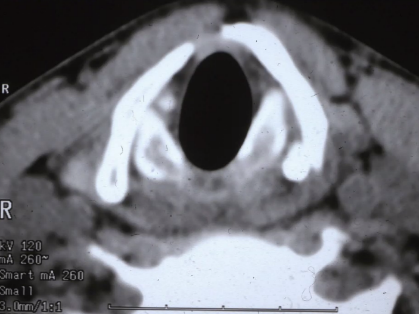

Hematotympanon, benfraktur genom temporalbenet. Som gått in i mellanörat och fyller ut med blod ex. Dålig hörsel. Vad har temporalfrakturen orsakat för effekter, nerver från innerörat till hjärnstam, fascialis, hörsel, balansnerv (övre och undre) – akut yr om någon av dessa är comprimized

Hur ska tänka kring tvärfraktur och längsmedfraktur på temporalbenet?

A

Större risk att nerver som ex fascialis är skadad vid tvärsfraktur (jämfört med längsmed)